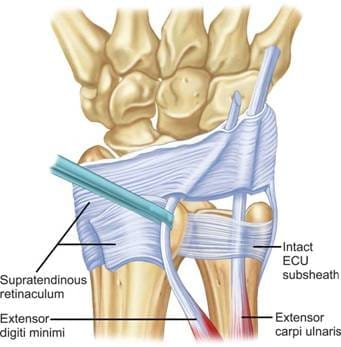

ECU腱は、手首を伸ばしたり、小指側へ動かしたりする働きをもつ重要な腱です。特に、手首をひねる動作、ラケットやゴルフクラブを振る動作、強く物を握って手首を固定する動作で大きな役割を果たします。論文では、ECU腱は手関節の尺側にある第6コンパートメントを通り、専用のトンネルと腱鞘様構造(subsheath)によって安定化されていると整理されています。

この安定化機構が壊れると、ECU腱は本来の位置からずれ、亜脱臼や脱臼を起こします。すると、手首の小指側に痛みが出るだけでなく、「コキッ」「パキッ」といった違和感や引っかかり感が生じることがあります。

亜脱臼・脱臼

腱を支えるsubsheathが破綻し、腱が本来の溝から外れてしまう状態です。クリック感や不安定感を伴うことがあります。

この論文の中心テーマは、ECU腱不安定症に対する手術法です。内容を簡単にまとめると、手術では主に破れたsubsheathの修復、あるいは伸筋支帯を使った再建が行われます。

論文では、解剖学的修復と非解剖学的再建の両方が紹介されていますが、伸筋支帯の一部を用いた再建は広く行われ、良好な成績が報告されているとされています。